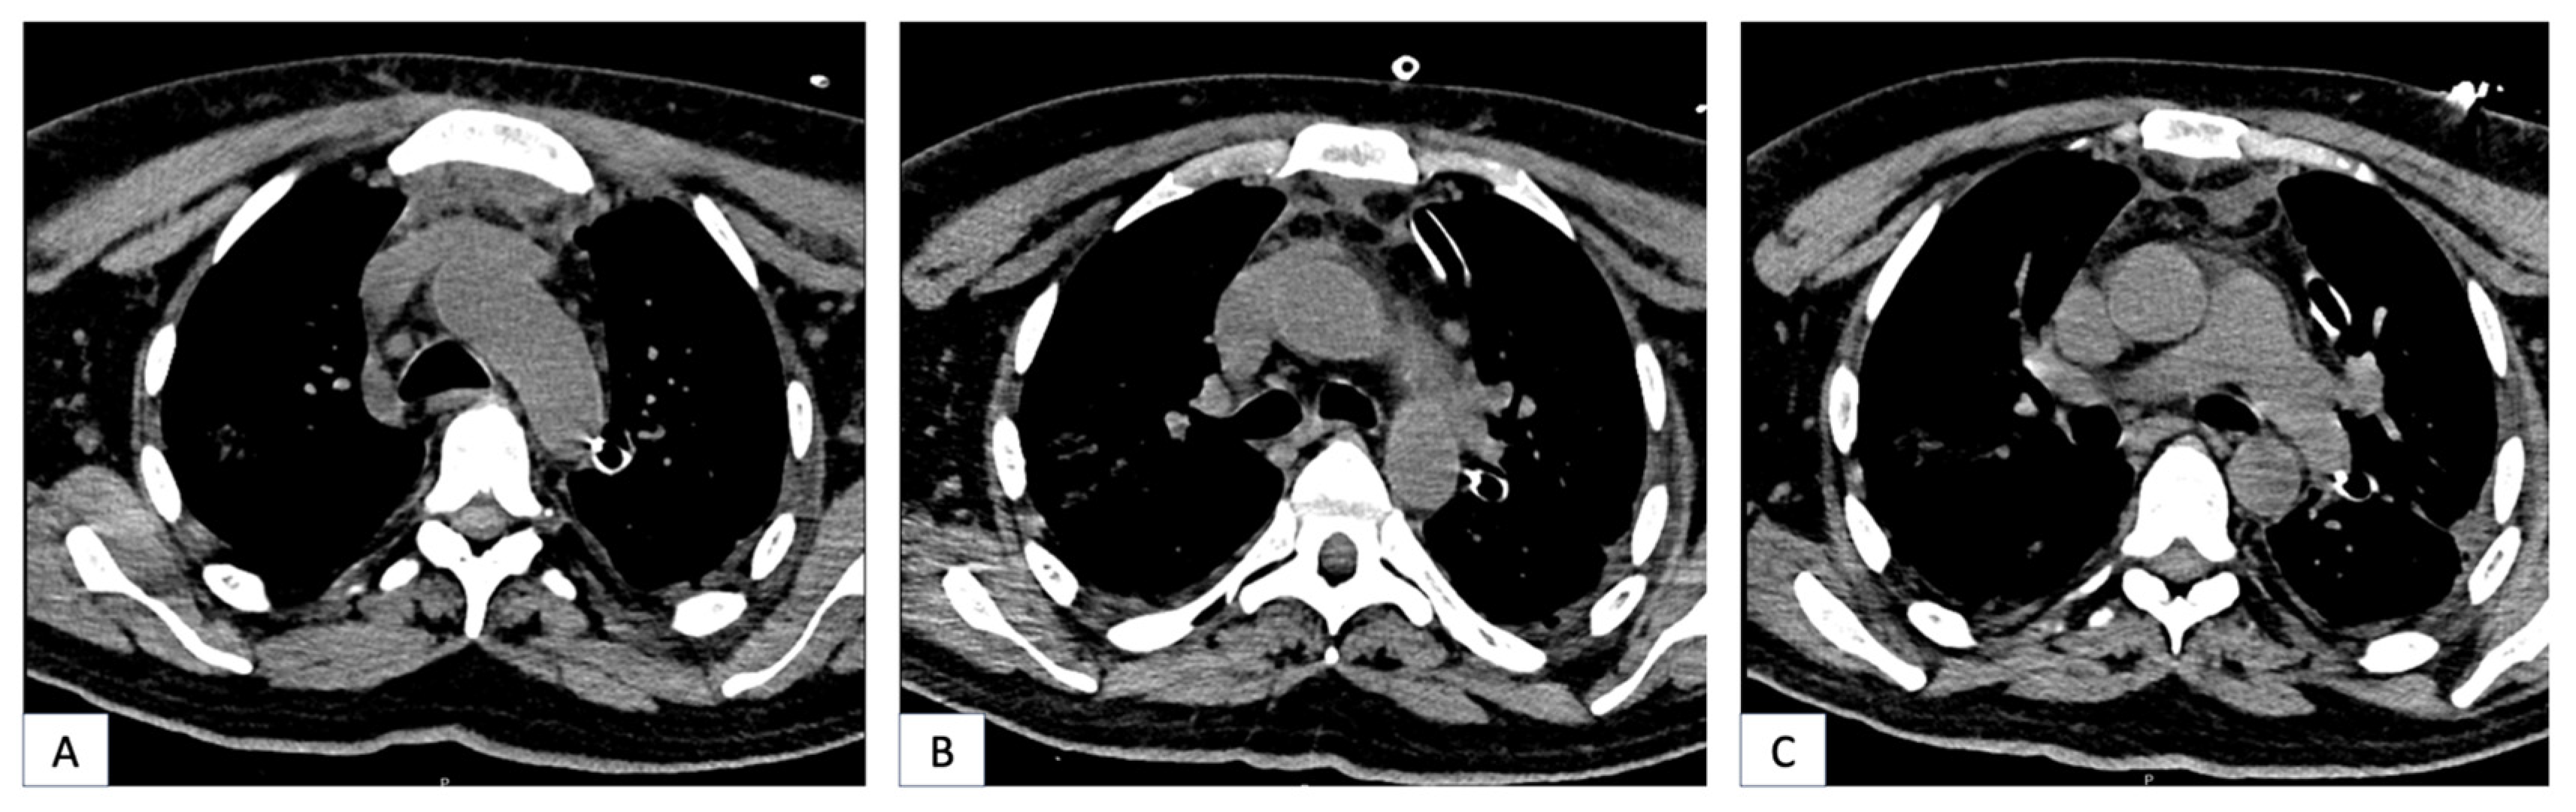

Preoperative radiographic images of two patients with DNM showing signs of neck and mediastinal involvement are shown in Figure 1 and Figure 2.

Figure 2.

(A–C): Chest CT of a 43-year-old patient showing mediastinal involvement of DNM. The patient was treated with left cervicotomy and underwent a left thoracotomy for mediastinal drainage.